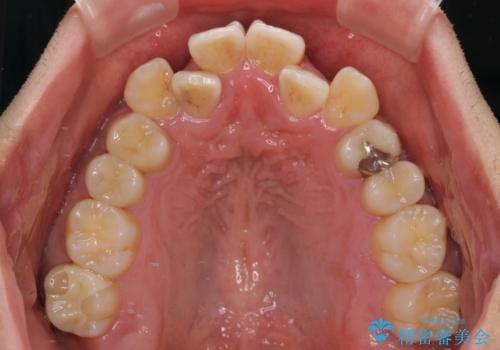

上下の前歯部に強い叢生(ガタガタの歯並び)があり、そのまま歯を並べると出っ歯になってしまう可能性がありました。

そこで、上下左右の第一小臼歯を抜歯し、歯が並ぶためのスペースを確保し叢生を解消する治療計画を立てました。